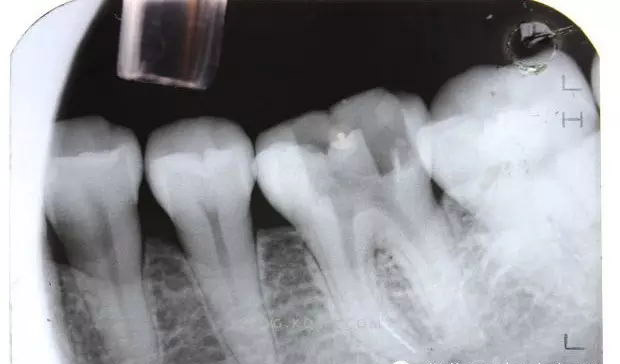

(1)通路建立:臨床操作中,X線明確斷針位置后,在根管顯微鏡(放大10~20倍)觀察下,先用帶柄根管銼插入根管,直到斷針冠方斷面,用止動片標(biāo)記,確定斷針深度。然后用K銼或者H銼將斷針上部的根管預(yù)備到30~40#,將GG鉆2#和3#尖 端磨平,使GG鉆尖 端平面的直徑大于斷針的直徑,用2?;蛘?#調(diào)磨后的GG鉆從根管口預(yù)備到斷針的位置,建立通道,使斷針以上部分根管明顯通暢,便于顯微鏡觀察和術(shù)中操作。